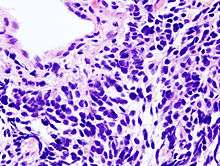

Lung cancers are classified according to histological type.[12] This classification is important for determining management and predicting outcomes of the disease. Lung cancers are carcinomas—malignancies that arise from epithelial cells. Lung carcinomas are categorized by the size and appearance of the malignant cells seen by a histopathologist under a microscope. For therapeutic purposes, two broad classes are distinguished: non-small-cell lung carcinoma and small-cell lung carcinoma.[65]

In small-cell lung carcinoma (SCLC), the cells contain dense neurosecretory granules (vesicles containing neuroendocrine hormones), which give this tumor an endocrine/paraneoplastic syndrome association.[68] Most cases arise in the larger airways (primary and secondary bronchi).[13] Sixty to seventy percent have extensive disease (which cannot be targeted within a single radiation therapy field) at presentation.[6]